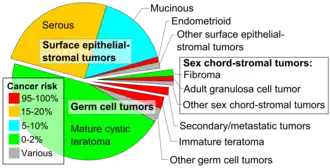

They are a type of germ cell tumor (a tumor that begins in the cells that give rise to sperm or eggs).[4][8] They are divided into two types: mature and immature.[4] Mature teratomas include dermoid cysts and are generally benign.[8] Immature teratomas may be cancerous.[4][9] Most ovarian teratomas are mature.[10] In adults, testicular teratomas are generally cancerous.[11] Definitive diagnosis is based on a tissue biopsy.[2]

Teratomas occur in the coccyx in about one in 30,000 newborns, making them one of the most common tumors in this age group.[5][7] Females are affected more often than males.[5] Ovarian teratomas represent about a quarter of ovarian tumors and are typically noticed during middle age.[10] Testicular teratomas represent almost half of testicular cancers.[13] They can occur in both children and adults.[14] The term comes from the Greek word for "monster"[15] plus the "-oma" suffix used for tumors.